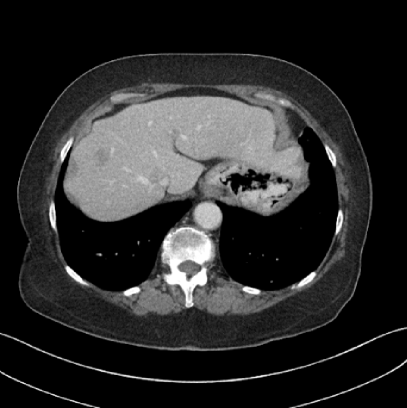

V.B. Clinical Cases

None of the spatial resolution and artifact reduction advantages would hold unless JENG shows image quality improvement over the clinical standard method on patient datasets. To do so, we evaluated JENG on 5 thoracic and 3 abdominal CT scans and all scans used the same parameter settings as those for the ACR phantom scan, except that the tube current and the pitch is modulated individually for each patient. The exact experiment setup was discussed in Sec. IV.. For a fair image quality comparison, we matched the resolution of JENG and the clinical standard hybrid IR and studied their image noise and artifacts.